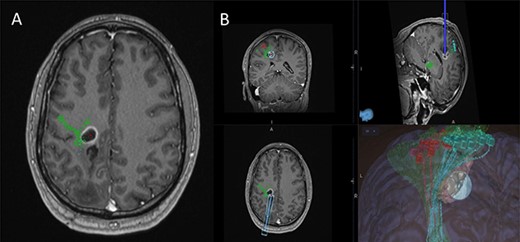

(A) Axial T1-weighted image with gadolinium showing the lesion with imposed DTI tractography of the CST; (B) planned trajectory for insertion of the tubular retractor guided by the preoperative integrated anatomical and functional motor mapping.

A 42-year-old, right-handed gentleman presented with 1-month history of right foot weakness and focal seizures. Imaging revealed a 1.6 × 1.4 × 1.6 cm enhancing lesion in the left corona radiate (Fig. 1). He underwent stereotactic frameless needle biopsy using the method previously described by our group [6]. The biopsy result was inconclusive, the procedure was uneventful and he recovered without neurological deficit. Post-operative computed tomography (CT) showed the biopsy site was posterolateral to the lesion and following discussion in our neuro-oncology multidisciplinary team meeting the consensus was to perform an open biopsy.

Preoperative cortical and subcortical motor mapping was performed (Fig. 2). Diffusion tensor and spherical deconvolution tractography was used to delineate the anatomy of the CST bilaterally. Tensor-derived metrics were calculated for both CSTs. The fractional anisotropy and the hindrance-modulated orientational anisotropy of the left CST (tumour side) were lower. The axial, radial and mean diffusivities were higher in the left CST. Navigated TMS (NEXSTIM©; single pulse technique) was used to assess CST function. Abnormal interhemispheric RMT ratios (iRMTr) were found for both upper and lower limbs and an abnormal combined cortical excitability score (number of abnormal iRMTr)—2/2. This information suggested altered cortical excitability and microstructure of the CST on the side with the tumour.

Two independent techniques were used to dissect the ipsilateral CST with StealthViz Software (MEDTRONIC©): region of interest (ROI) technique and TMS-seeded technique. In the first one, two ROIs were defined, precentral gyrus and midbrain at the level of the superior cerebellar peduncle, the anatomical streamlines going through both regions were selected. In the second technique, the positive nTMS responses for the upper and lower limb were selected independently as ROIs and the other ROI was in midbrain at the level of the superior cerebellar peduncle. Both dissections of the CST were used as they provided an anatomical and functional assessment of the tract. The tumour was delineated in the Cranial Software (MEDTRONIC©) and the preoperative cortical and subcortical mapping was integrated in a 3D model (Fig. 2).